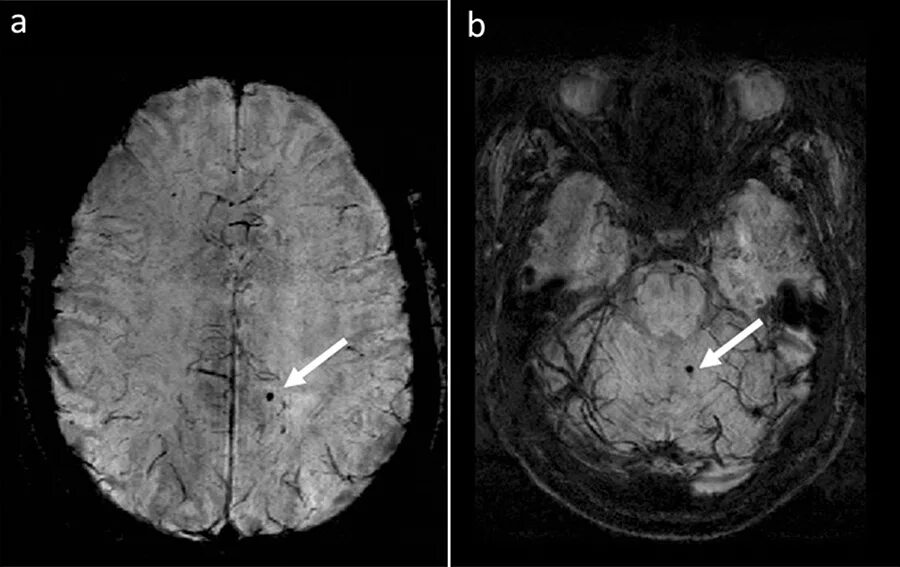

Атеросклероз артерий головного мозга симптомы